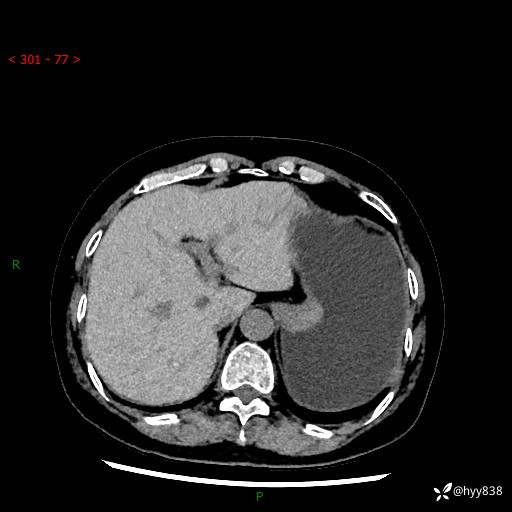

胃CT平扫+增强(动脉期+静脉期)

三期CT值:46hu 58hu 75hu